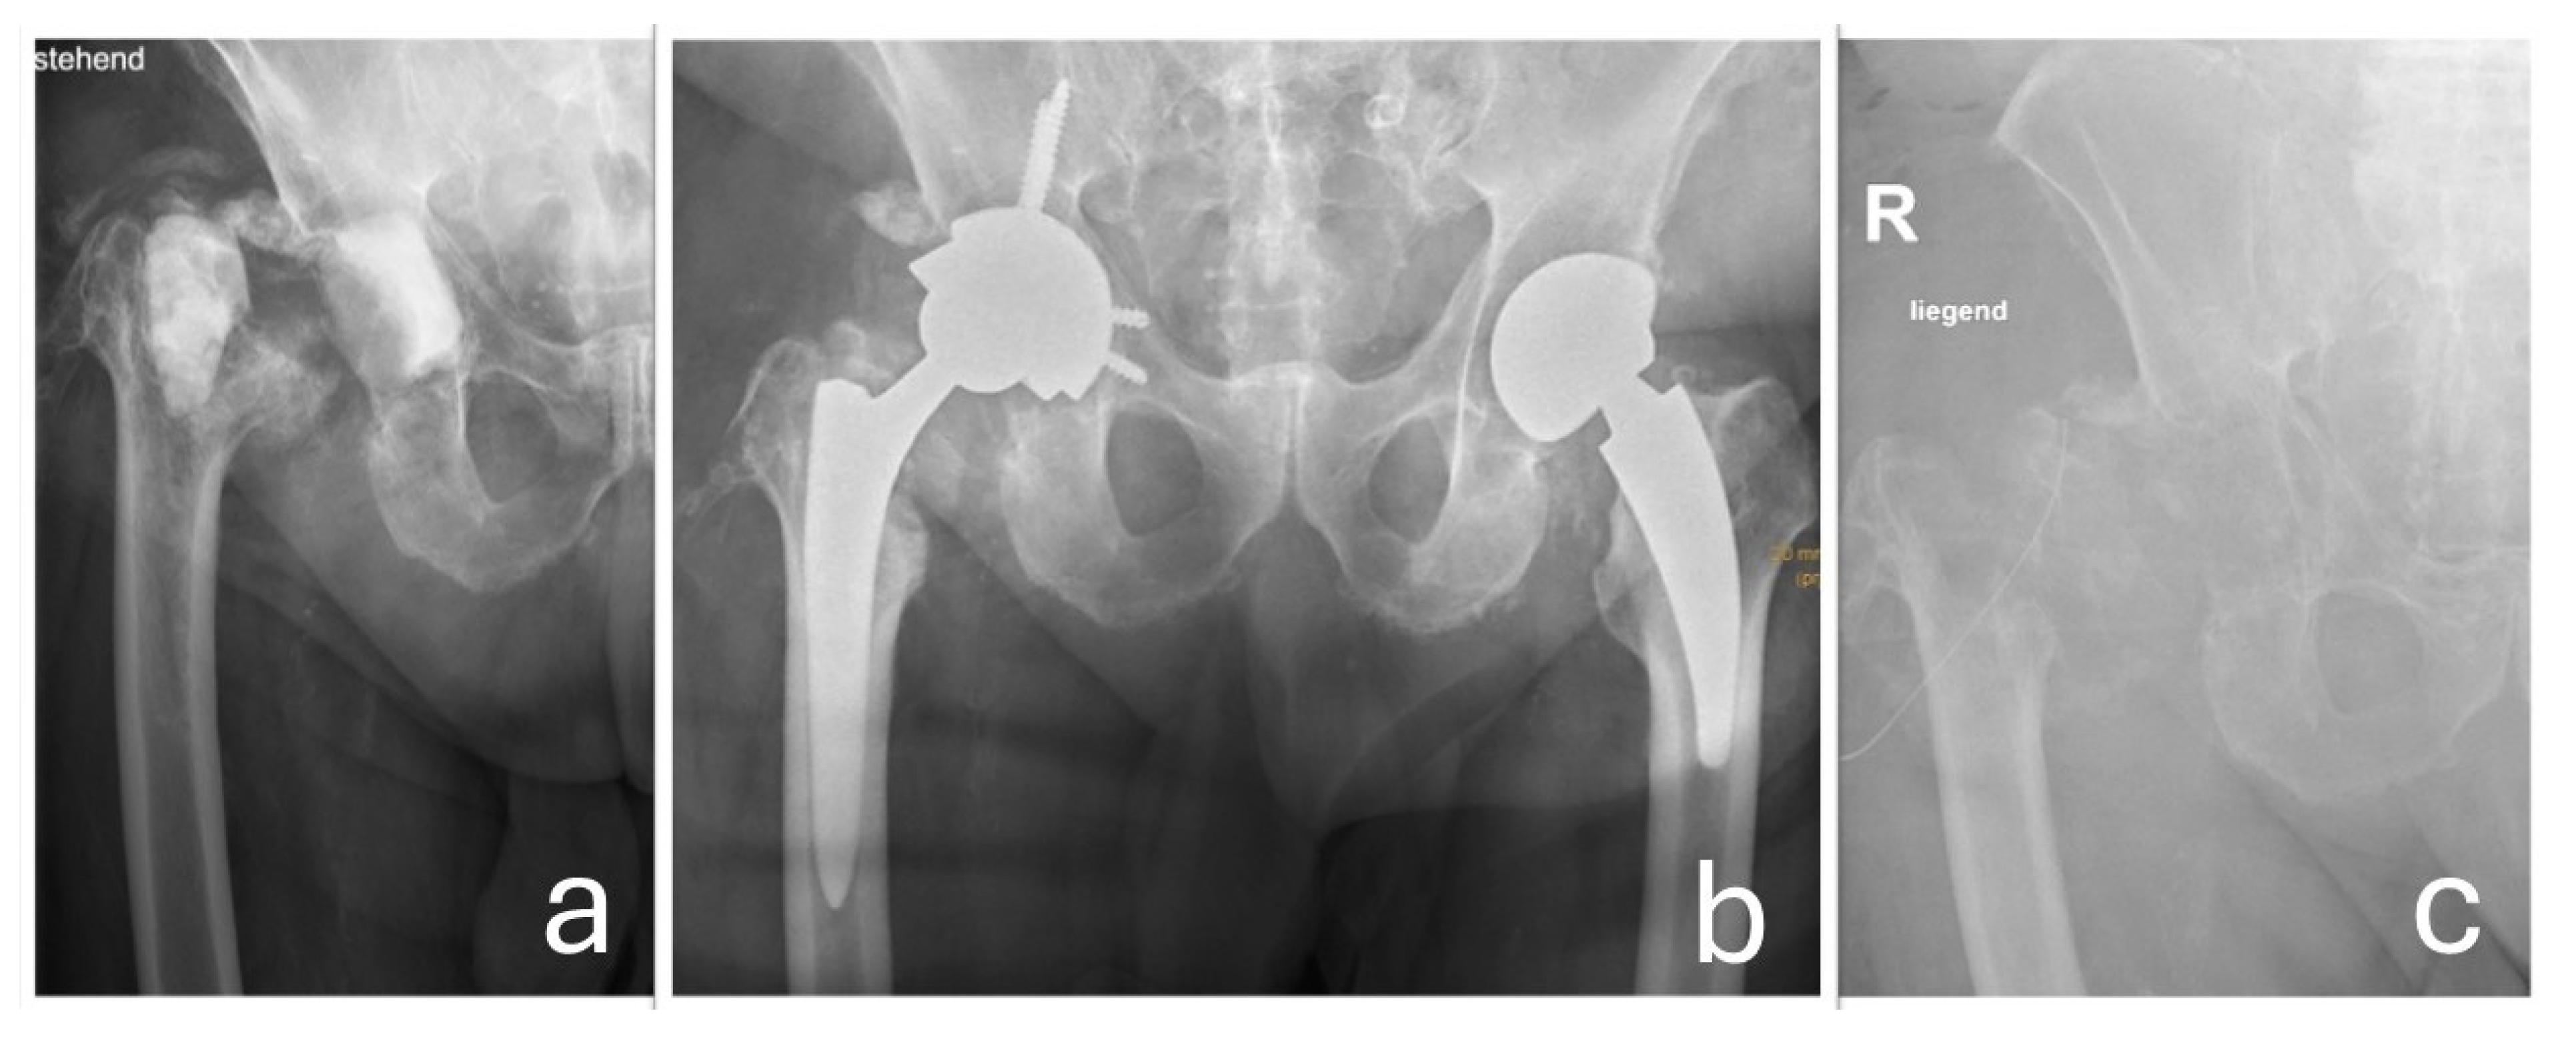

In 2017, a revision surgery was performed in the same hospital due to persistent hip joint pain and radiologically evident eccentric wear of the liner in the primary load-bearing zone. The liner was replaced with highly cross-linked polyethylene and a new metal head (Figure 3).

The differential diagnosis pointed towards an excessive wear reaction from the hip implant, which had been in place for over 27 years. The reaction was thought to be the source of the tumor-like mass. The patient underwent surgery via two approaches: a pararectus approach to excise the main tumor, leaving a small residual mass adherent to the inguinal vessels, and an anterolateral approach for a revision of the hip joint. The procedures were performed by orthopedic and trauma surgeons, with vascular surgeons available on standby if required. An intraoperative histological frozen section revealed no indication of the presence of a malignant tumor. Macroscopic examination revealed only mild trunnion wear and corrosion at the femoral head–neck junction. Black pitting was observed at the head–neck junction; however, no other obvious surface damage was noted on the trunnion or on the corresponding contact area of the femoral head. As the femoral stem remained well-fixed intraoperatively, it was retained. The femoral head was replaced with a new ceramic component (Bioball®, Merete Medical GmbH, Berlin, Germany). Due to the unavailability of the original inlay and the presence of lytic cysts in the acetabulum, the acetabular component was revised. A new acetabular cup (Lima Delta-One TT; Lima Corporate, Villanova di San Daniele del Friuli, Italy) was implanted, secured with three bone screws and an angled spacer, along with an elevated rim liner. To optimize wear resistance and longevity, a highly cross-linked polyethylene liner infused with vitamin E was employed (Figure 5). Multiple tissue samples were taken during surgery, confirming the presence of an implant wear reaction.

Postoperatively, there was notable improvement in lower extremity swelling, attributed to decompression of the neurovascular bundle. However, further diagnostic workup revealed a bacterial infection caused by methicillin-resistant Staphylococcus aureus (MRSA), confirmed through implant sonication, tissue cultures, and PCR analysis. Targeted antibiotic therapy was initiated according to the antibiogram, but the infection persisted despite appropriate treatment. As a result, a two-stage revision procedure was performed. This included thorough resection of residual pseudotumor tissue surrounding the neurovascular bundle and placement of a temporary, non-articulating, antibiotic-loaded cement spacer. Reimplantation was postponed for six months due to additional complications, including a nosocomial pulmonary infection and urinary tract infection caused by E. coli and Pseudomonas. Once these infections were resolved, reimplantation was successfully performed using a Lima Delta Multihole TT acetabular component, secured with bone screws, an angled spacer, a protrusively designed liner, a 36 mm XL ceramic femoral head, and an SL-Plus MIA high-offset femoral stem (Smith & Nephew). Unfortunately, reinfection with Enterobacter cloacae complex occurred post-reimplantation, ultimately necessitating joint resection (Figure 7).

Figure 3. (a) The eccentric position of the prosthetic head is visible, indicating wear-related reaction of the sandwich-type inlay (metal shell encased in a polyethylene liner) in the main load-bearing zone. Additionally, heterotopic ossifications around the hip joint are observed. (b) The condition after the head/inlay exchange. The new metal head is now centrally positioned in the cross-linked polyethylene insert.

Figure 7. (a) The status post explantation of the prosthetic components with a non-articulating cement spacer in place. (b) The situation following delayed reimplantation of the total hip arthroplasty. Due to recurrent infection, a second explantation of the hip prosthesis was required, as shown in (c).